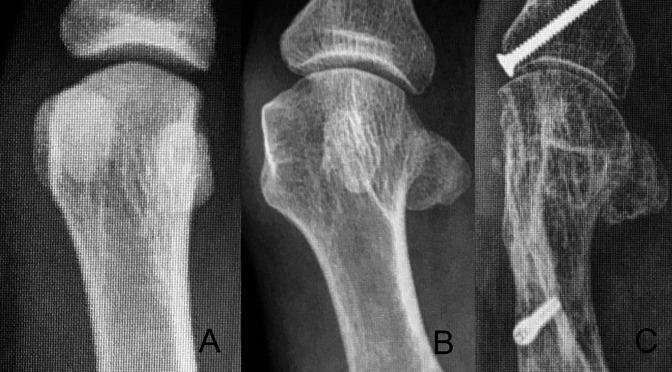

Hallux valgus deformity is a multiplanar deformity, where the rotational component has been recognized over the past 5 to 10 years and given considerable importance. Years ago, a rounded shape of the lateral edge of the first metatarsal head was identified as an important factor to detect after surgery because a less rounded metatarsal head was associated to less recurrence. More recently, pronation of the metatarsal bone was identified as the cause for the rounded appearance of the metatarsal head, and therefore, supination stress was found to be useful to achieve a better correction of the deformity. Using CT scans, up to 87% of hallux valgus cases have been shown to present with a pronated metatarsal bone, which highlights the multiplanar nature of the deformity. This pronation explained the perceived shape of the metatarsal bone and the malposition of the medial sesamoid bone in radiological studies, which has been associated as one of the most important factors for recurrence after treatment. Treatment options are discussed briefly, including metatarsal osteotomies and tarsometatarsal arthrodesis.

拇外翻畸形是一种多平面畸形,其中旋转成分在过去 5 到 10 年中得到了认可,并受到了相当大的重视。多年前,人们发现第一跖骨头外侧缘的圆形形状是术后检测的一个重要因素,因为较不圆的跖骨头与较低的复发率相关。最近,跖骨的内旋被认为是跖骨头呈圆形的原因,因此,旋前应力被发现对实现畸形的更好矫正很有用。使用 CT 扫描,高达 87%的拇外翻病例显示出跖骨的内旋,这突出了畸形的多平面性质。这种内旋解释了在影像学研究中所感知的跖骨形状和内侧籽骨的错位,这被认为是治疗后复发的最重要因素之一。简要讨论了治疗选择,包括跖骨截骨术和跗跖关节融合术。